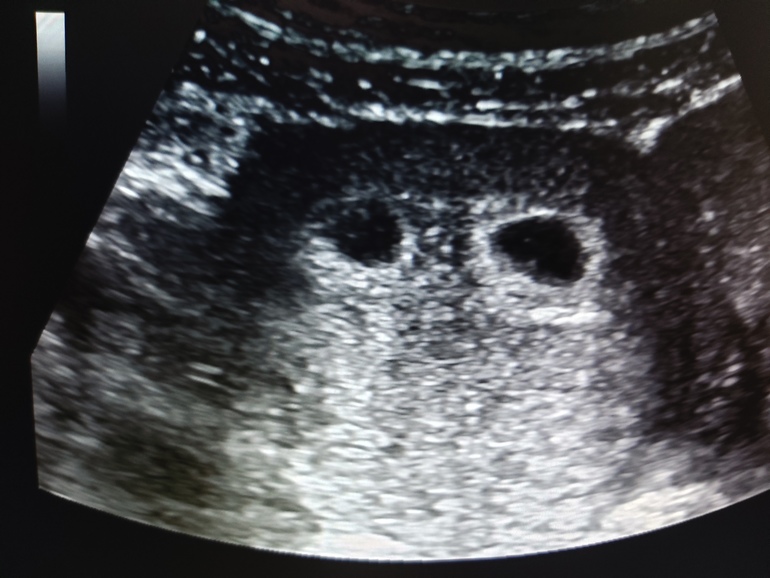

пост радости до луны и обратно! 🥳🙏🥰💃🤸♀️ узи 6 недель и 3 дня

два плодных яйца 6 дней назад были 4.3 и до 5 мм, сегодня одно пя 12х7х8 🤗 другое 10х6х9 🤗

пульсирует сердцебиение ❤❤ у обоих эмбрионов !!!

ни отслоек ни гематом по крайней мере не видно.